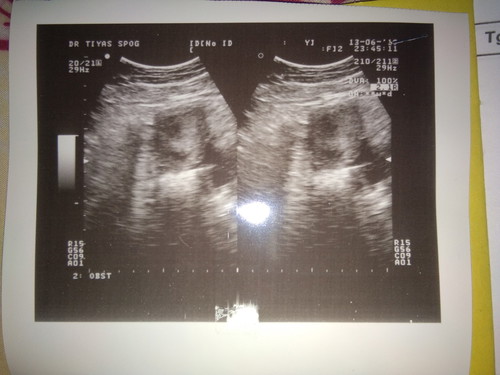

Hasil USG

Doain bulan depan ada perkembangan ya bunda Ini masih terlihat kantong nya aja katannya dokternya..

Saya waktu pertama x tau hamil UK 5w 5d. Masih terlihat kantung saja. Insyaallah hari Senin nanti mau USG lg di UK 12 w. Mudah² udh ada utun dan djj nya. Doain juga ya kawan²... Buat bunda. Semoga di USG selanjutnya udh bisa liat janin nya juga... 🙏

Amin bunda, aku jga kemarin 8 minggu hanya kantung janinnya aja yg keliatan dan alhamdulillah pas 12 minggu sdh ada Jantungnya bunda, tetap berdoa dan semangat ya bun 💓💓💓

Aamiin, semoga ada perkembangan ya bun.. Nnti 6-7week insyaAllah udh keliatan janinnya kok bun

Saya 5 mggu aja belum keliatan apa2 bun.. Semoga kontrol selanjutnya ud keliatan babynya ya